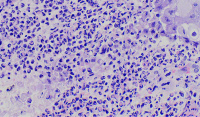

外阴多发赘生物,请教老师们,怎么报告?

性别

女

年龄

62

临床诊断

一般病史

发现外阴数十粒丘疹样结节,伴溃疡

标本名称

外阴丘疹样赘生物

大体所见

灰白色组织两粒0.5*0.3cm

考虑:疱疹病毒感染

疱疹性皮炎。

符合疱疹性皮炎。